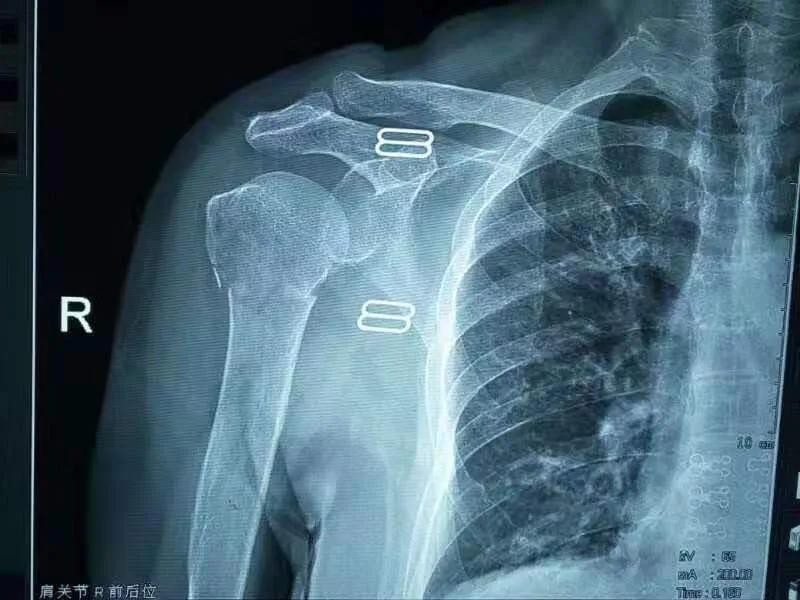

四、肱骨骨折X线图

肱骨骨折根据发生部位的不同分为肱骨外科颈、肱骨干、肱骨髁上、肱骨髁间、肱骨外髁、肱骨内上髁。